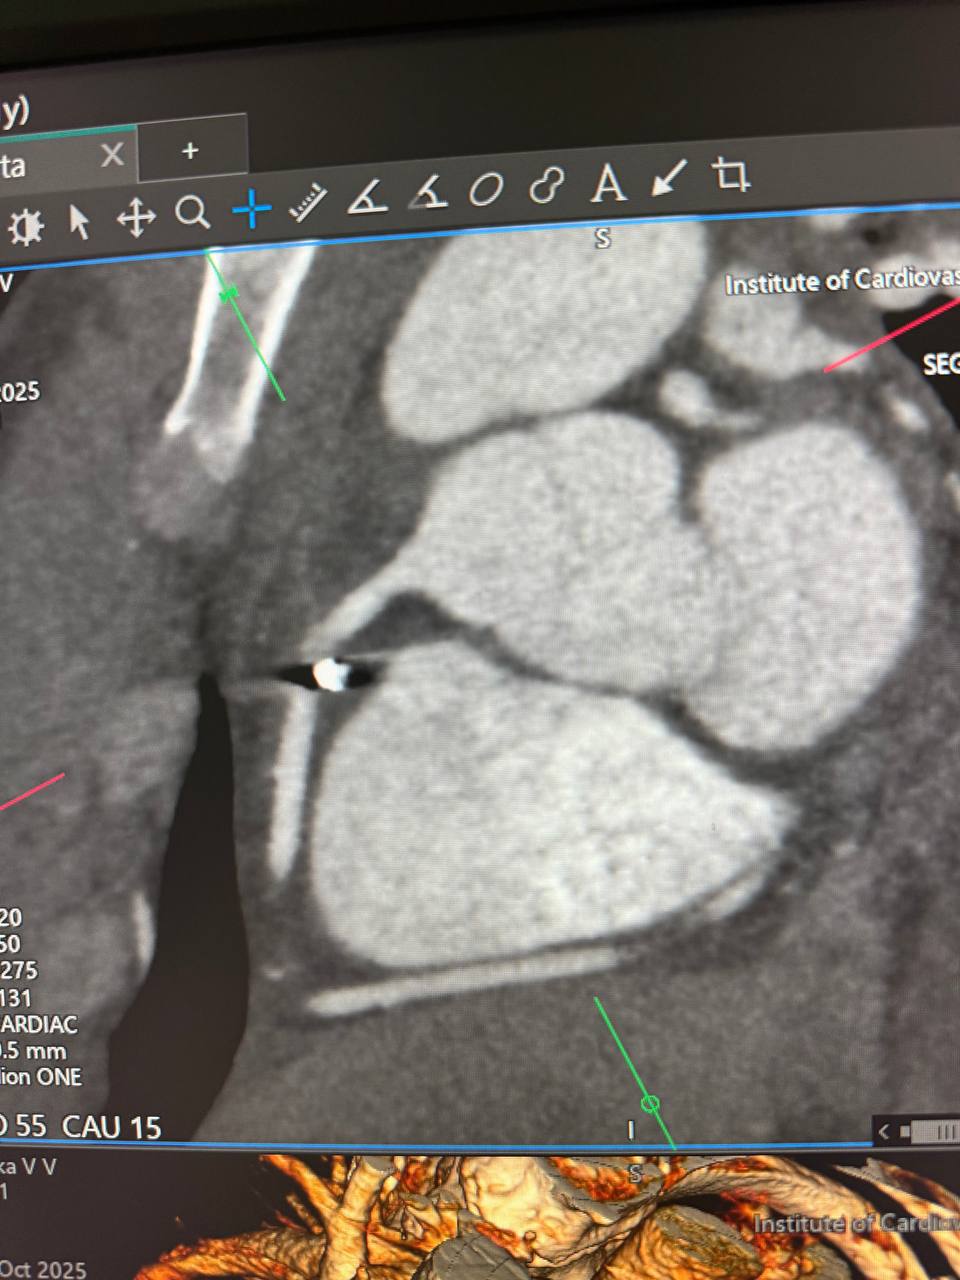

Металевий уламок застряг у правій атріовентрикулярній борозні, біля правої коронарної артерії. Це надзвичайно небезпечна зона, де кожен рух може коштувати життя.